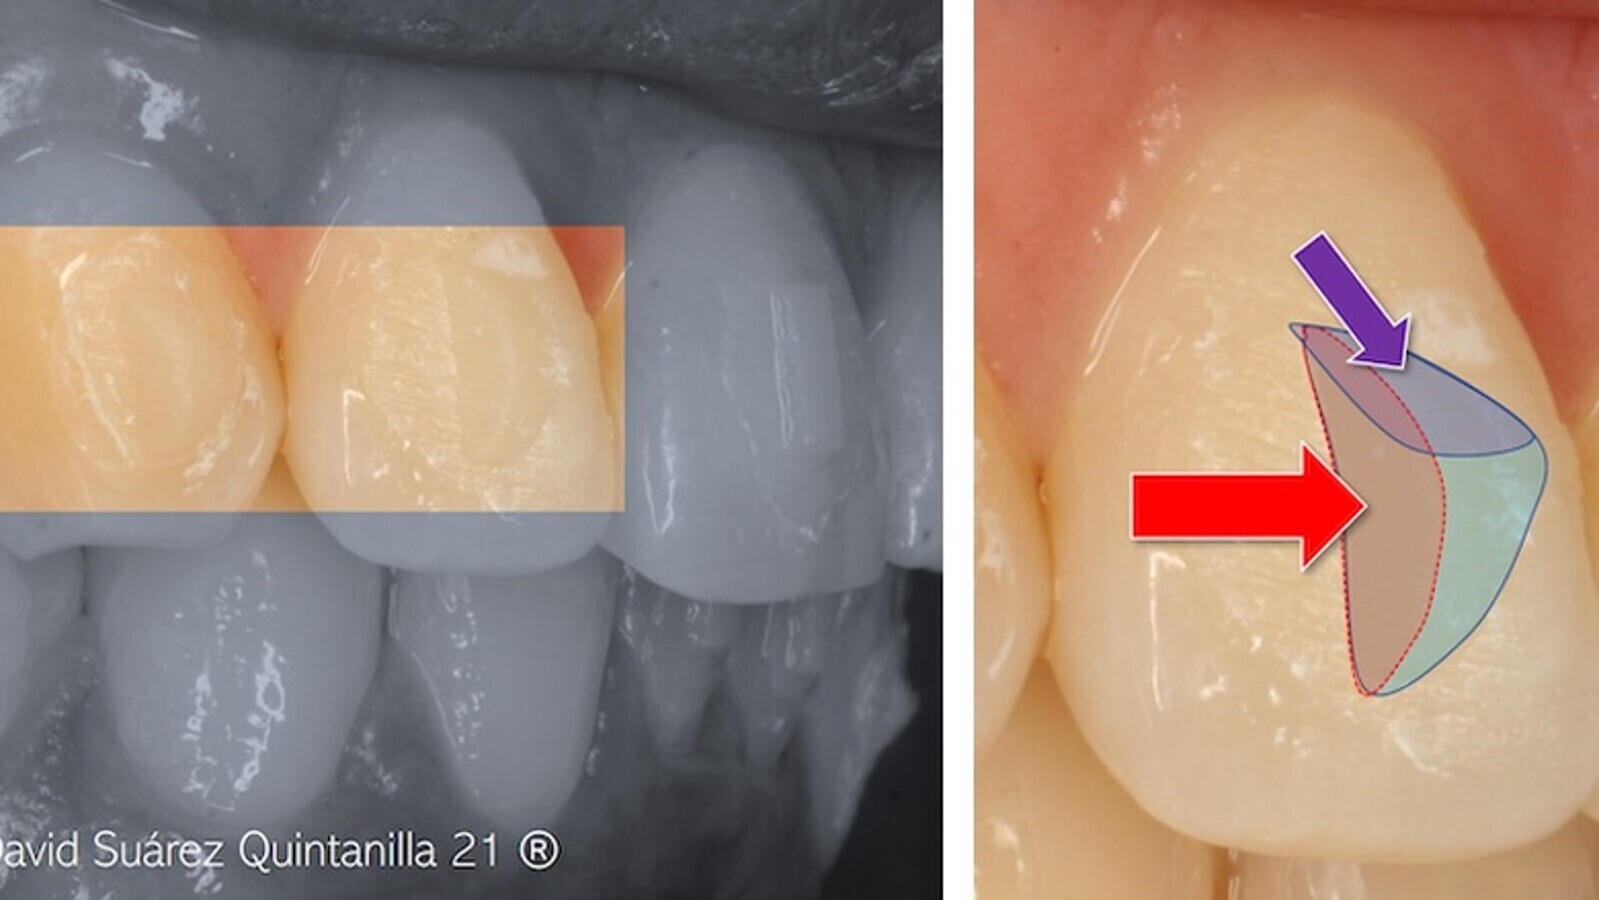

hay que tener cuidado con los recovecos interproximales, en especial en los dientes muy rotados. La elevación o arco de torque sirve para potenciar el movimiento radicular positivo de torsión, combinado con un punto de presión inciso-lingual; puede incorporarse al diseño digital o aplicarse directamente en el plástico por medio de alicates (ver la figura 56).

Figura 56. La elevación o arco de torque sirve para potenciar el movimiento radicular positivo de torsión, combinado con un punto de presión inciso-lingual.

Es importante analizar el eje mayor del diente y la colocación del atache respecto al mismo, así como los pares de fuerzas que se generan en las distintas facetas activas (figura 58).

Figura 58. Análisis del eje mayor del diente y de la colocación del atache respecto al mismo, así como de los pares de fuerzas que se generan en las distintas facetas activas.